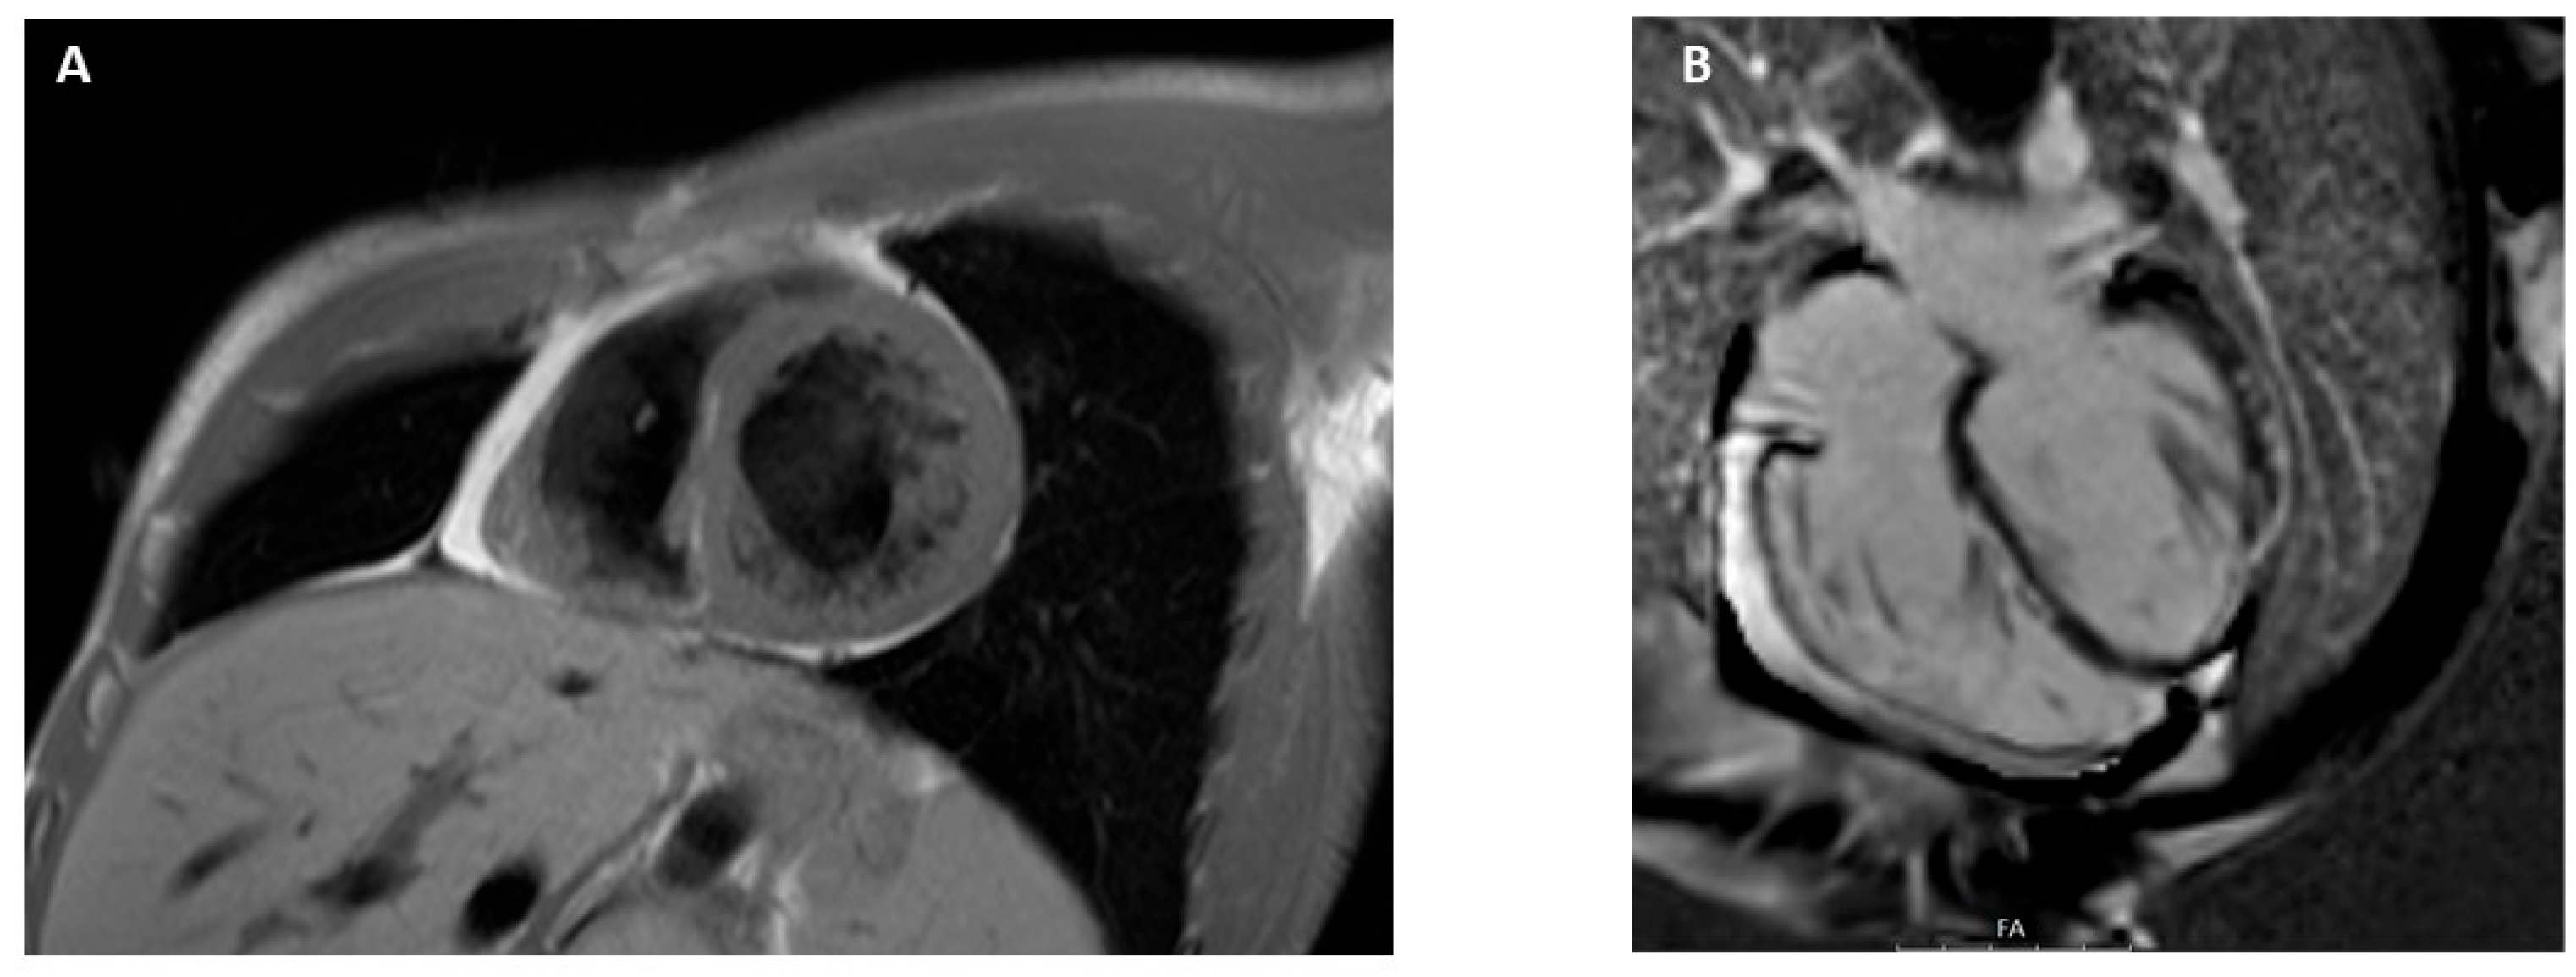

3.9. Arrhythmogenic Cardiomyopathy